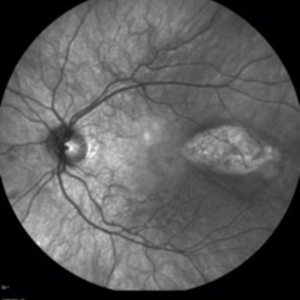

Fundus autofluorescence imaging of an asymptomatic 12-year-old girl with torpedo maculopathy of the left eye.

Photographer: Pierre-Henry Gabrielle, Ophthalmology department, Dijon University Hospital, France

Imaging device: Heidelberg Spectralis

Condition/keywords: fundus autofluorescence (FAF), torpedo maculopathy